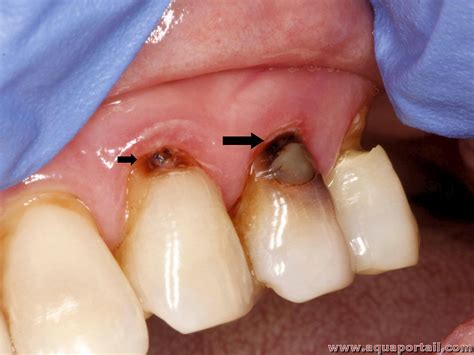

Carie définition et explications

Carie définition et explications from www.aquaportail.com